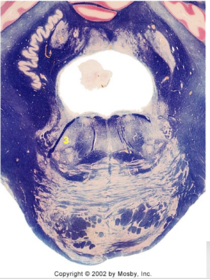

| Head of caudate | |

| Anterior commissure | |

| Thalamus | |

| Substantia nigra | |

| Optic tract | |

| Dentate nucleus | |

| Pons | |

| Longitudinal pontine fibers | |

| Uncus | |

| Superior cerebellar peduncle | |

| Red nucleus | |

| Corticospinal tract (dark) | |

| Pontine nuclei (pale) | |

| Transverse pontine fibers (dark) | |

| Inferior olive | |

| CTT | |

| Medial lemniscus | |

| Nucleus cuneatus | |